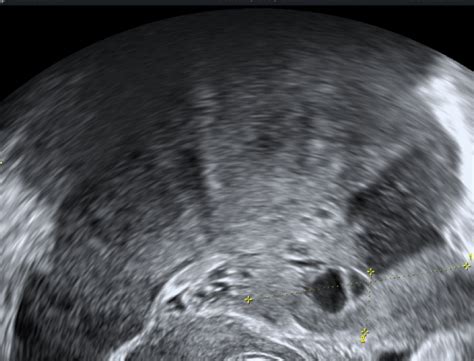

- Policistični videz jajčnikov na ultrazvoku: Jajčniki so povečani in vsebujejo večje število majhnih foliklov (običajno 12 ali več v enem prerezu), ki so pogosto razporejeni ob robu jajčnika. Vendar pa sama prisotnost policističnih jajčnikov (PCO) še ne pomeni PCOS.